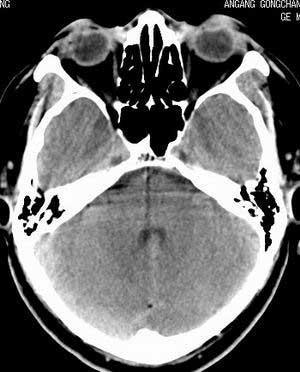

增强扫描:

平扫右侧岩骨与枕骨交角内侧脑质内见淡片状密度增高影,内缘清晰。增强图象上未见明显显示。

右枕颅骨内板下高密度应该是窦的变异,和其症状应该无关,根据病史另找原因吧。[em16]

条状高密度为小脑幕吧

条状高密度为小脑幕